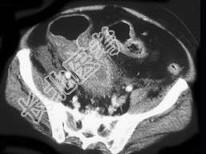

- 单项选择题男,18岁, 患者皮肤挫伤,用林可霉素预防感染, 次日大便次数增多、出现粘液便,结合图像应考虑为 ( )

B、假膜性肠炎